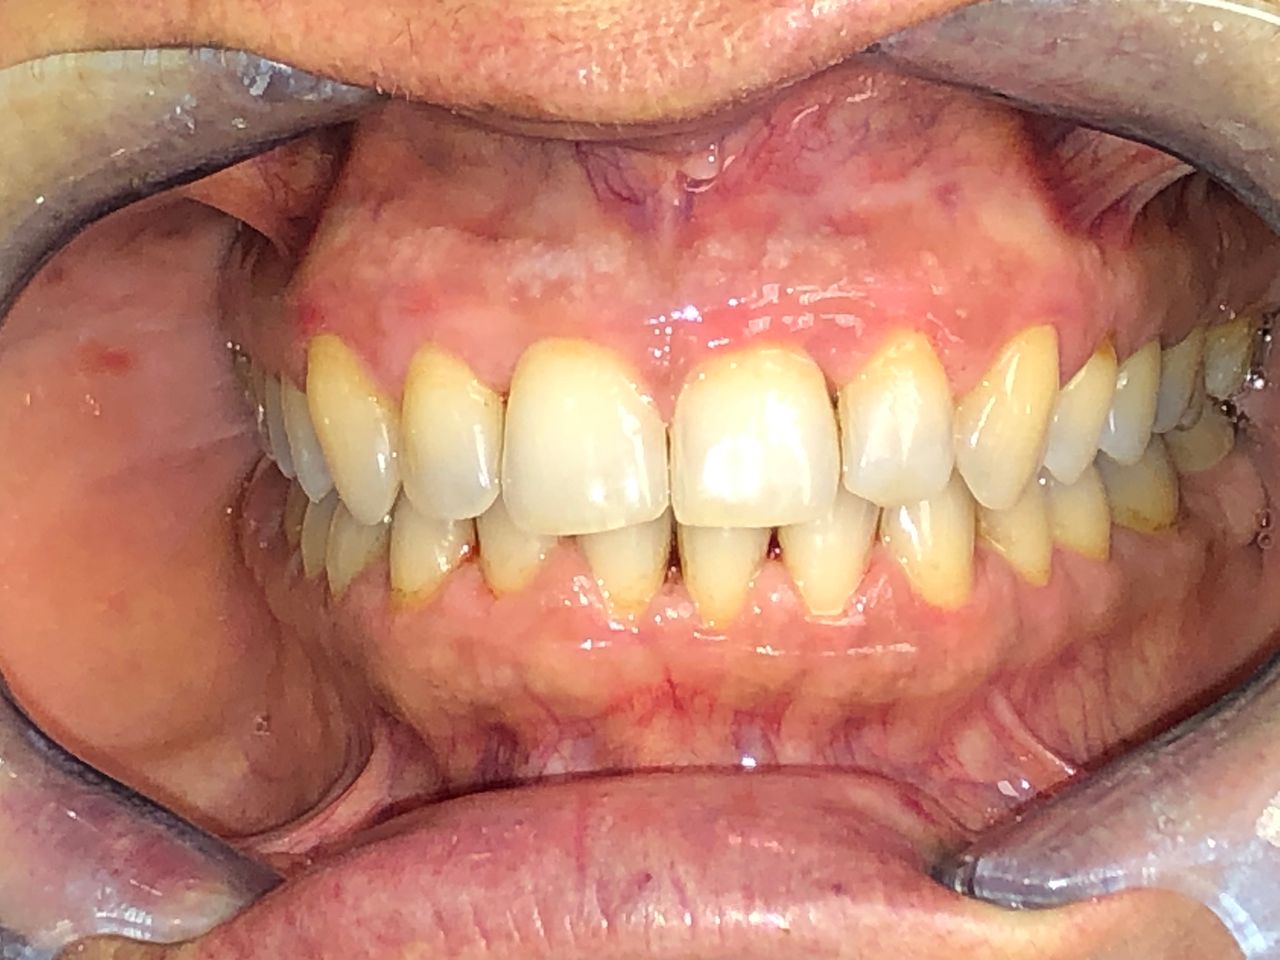

Foto e video

• M

Il Dottor Luca Strazioso ha qualità rare; mi ha ascoltata attentamente sin dal primo appuntamento, con la sua pazienza, competenza e professionalità durante ogni seduta ha ricostruito il mio sorriso, mi ha ridato la sicurezza che ormai avevo perduto. Posso affermare di essere rinata grazie alle sue mani, alla sua intelligenza e sensibilità. Inoltre, la Signora Antonella, assistente alla poltrona, è assolutamente insostituibile e generosa. Infinitamente grata ad entrambi.

• Studio Dentistico LUCA STRAZIOSO implantologia  •